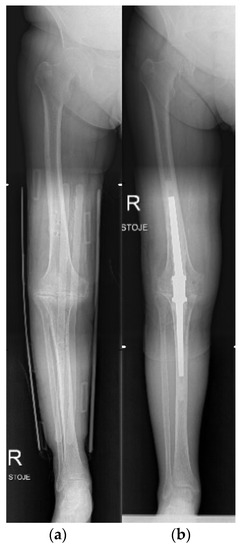

3.6. Knee

- Kanakamedala, A.C.; Hurley, E.T.; Manjunath, A.K.; Jazrawi, L.M.; Alaia, M.J.; Strauss, E.J. High Tibial Osteotomies for the Treatment of Osteoarthritis of the Knee. JBJS Rev. 2022, 10, e21.00127. [Google Scholar] [CrossRef]

- Wolcott, M.; Traub, S.; Efird, C. High Tibial Osteotomies in the Young Active Patient. Int. Orthop. 2010, 34, 161–166. [Google Scholar] [CrossRef] [PubMed]

- Gomoll, A.H. High Tibial Osteotomy for the Treatment of Unicompartmental Knee Osteoarthritis: A Review of the Literature, Indications, and Technique. Phys. Sportsmed. 2011, 39, 45–54. [Google Scholar] [CrossRef] [PubMed]